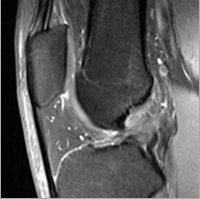

IRM

La constitution de l’image IRM repose sur l’interaction d’un champ magnétique et d’une radiofréquence sur l’orientation des atomes d’hydrogènes (protons). L’aimant permet d’orienter tous les protons dans une même direction. Ceux-ci sont ensuite écartés de cette direction grâce à l’énergie donnée par une radiofréquence générée par une antenne. L’émission de l’antenne s’interrompant, les protons reprennent leur position d’équilibre dans le champ magnétique (relaxation) en redonnant de l’énergie qui peut être lue par une même antenne. L’antenne est spécifique aux régions anatomiques explorées : cerveau, rachis, articulations. Les relaxations T1 et T2 des protons dépendent des tissus, ceci permet d’obtenir deux images de contraste différent des différents tissus. Ces images sont appelées images pondérées T1 et T2. En IRM, il n’existe pas d’échelle de densité, on parle d’hyper ou d’hypointensité (ou signal) en T1 ou en T2 en fonction de l’aspect d’un tissu quelconque par rapport aux tissus adjacents. L’examen dure de 10 à 20 minutes par « séquences » de 2 à 3 minutes pendant lesquels il ne faut pas bouger. Il est conseillé d’avoir des boulquiès car l’IRM est une machine très bruyante. La seule contre-indication absolue à l’IRM est le pace-maker.

Arthro-IRM

On injecte dans l’articulation un produit de contraste à base de gadolinium avant l’IRM afin d’améliorer l’analyse des cartilages, des ménisques lorsqu’ils ont été opérés, les ligaments au niveau du genou, les tendons de la coiffe des rotateurs ou le bourrelet glénoïdien à l’épaule, le bourrelet cotyloïdien à la hanche ou rechercher des corps étrangers intra-articulaires.

Le produit de contraste est injecté par le radiologue en salle de radiographie et l’IRM est réalisée dans la demi-heure qui suit. Lorsque l’injection est réalisée par des radiologues expérimentés, elle est peu douloureuse et le geste est très rapide. Le patient n’est piqué qu’une fois. Le produit de contraste peut entraîner une réaction allergique dans de très rares cas. Ainsi, chez les patients allergiques, on prescrit un traitement antihistaminique à prendre trois jours avant l’examen.